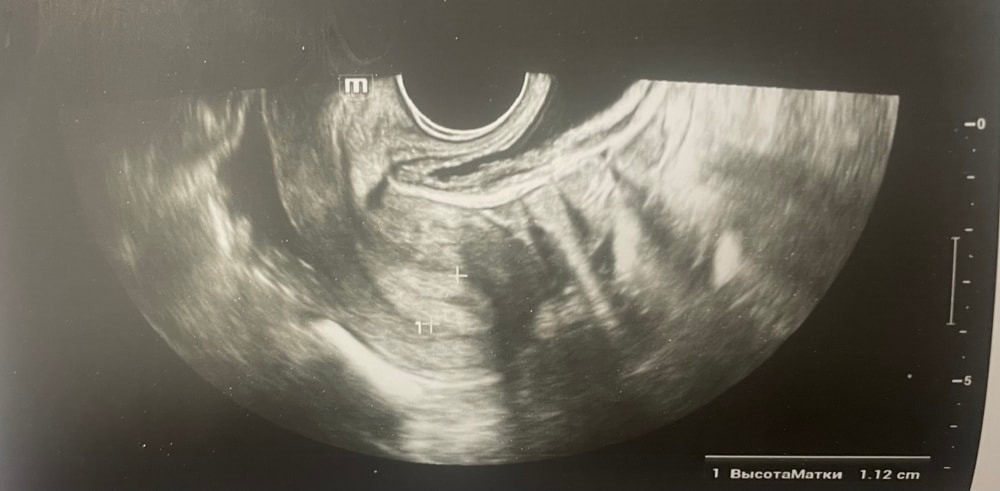

Прошу советаДобрый день, мы с мужем планируем беременность и в этом месяце произошло что то странное… дата начала последней менструации 4 октября закончилась 8, овуляцию отслеживала всю неделю почти сначала были бледные еле заметные полоски, 23 октября жирные четкие полоски, 24 октября стала чуть бледнее но яркая, вообщем положительный ещё был, с 25 числа тест уже отрицательный, через день после овуляции 26 числа стала странно себя чувствовать и во время овуляции болел живот то справа то с лева и поясница, так через день после начали болеть соски грудь вообще не болела, живот то болит то нет и с поясницей также, позже появилась небольшая изжога, нога немеет правая не знаю с чем связано), все это началось за 2 недели до месячных в середине цикла скажем так 29 числа пошла на узи спустя 6 дней грубо говоря гиня сказала что у меня была очень хорошая овуляция, что её признаки сохраняются до сих пор так скажем, желтое тело СПРАВО 20 мм, мои симптомы и все это очень похоже на беременность сказали большая вероятность, я очень была рада и надеялась, после узи появились выделения с комочками, до этого были просто густые белые выделения, утром тоже самое, пошла опять к гинекологу она сказала это может быть при ранец беременности сказала какие свечи купить, вечером я попала в не большое ДТП, удар был в поясницу и копчик, живот начал тянуть и поясница сильно болеть, начала болеть сама грудь помимо сосков, живот прошел относительно быстро, а вот поясница ломит до сих пор, решила сходить ещё раз на узи очень испугалась, на узи я пошла 31 через два дня после предыдущего и уже к другому гинекологу, моя на больничном, она сказала, что у меня отсутствуют даже косвенные признаки беременности и желтое тело с ЛЕВО А НЕ С ПРАВО, я не понимаю как такое может быть, очень расстроилась и совсем забыла про фото узи, она мне его не дала только заключение и как выяснилось уже не дадут оно не сохранилось, сказали переделывать, я очень доверяю своему гинекологу, но по заключению второго врача о беременности не может быть и речи в этом цикле, я не понимаю как желтое тело оказалось с лево если оно точно было справа в этом я уверена, а вторая врач уверяет во Братном, живот в обуляцию хоть и болел с двух сторон но больше справа помойму, вообщем я не понимаю есть ли шанс что я беременна или все таки нет, я понимаю что это слишком рано, до задержки ещё 4 дня, но мне плохо уже неделю по симптомам даже больше это же не просто так, я прикреплю фото заключения, могу ли я быть беременна, если посмотреть на эти заключения хотябы, подскажите пожалуйста фото узи относятся к 29.10, без фото 31.10